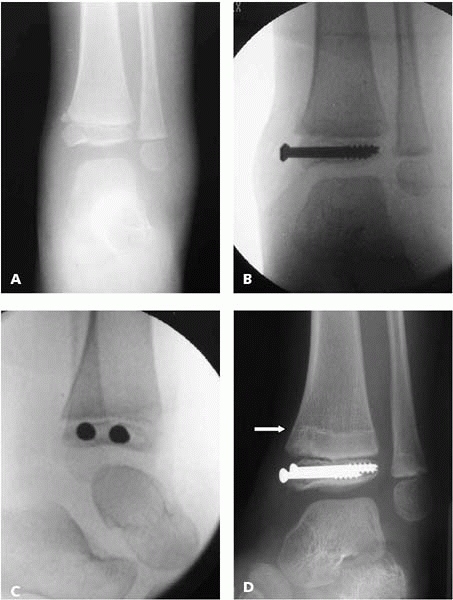

▪ FIGURE 9-15 A:

Displaced Salter IV fracture of the distal tibia in a 5-year-old. Unlike diaphyseal or metaphyseal fractures that will remodel with growth, fractures with displacement of the joint or physis should be treated aggressively with anatomic reduction and fixation. B,C: AP and lateral imaging intraoperatively ensure both screws are not in the joint or the physis. D: Ten months following the injury a growth arrest line parallel to the physis confirms normal growth of the physis. |